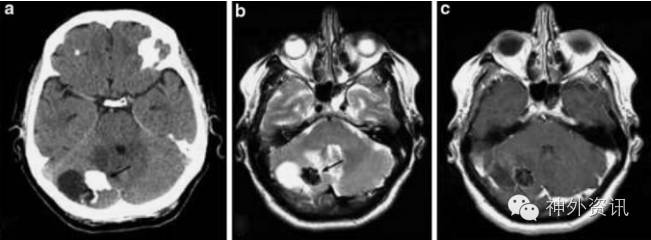

有文献报道,钙化性假瘤可并发室管膜瘤(图9)[4]、胚胎发育不良性神经上皮瘤[12]、脂肪瘤和胼胝体发育不良[13]等。

图9. 钙化性假瘤合并室管膜瘤。